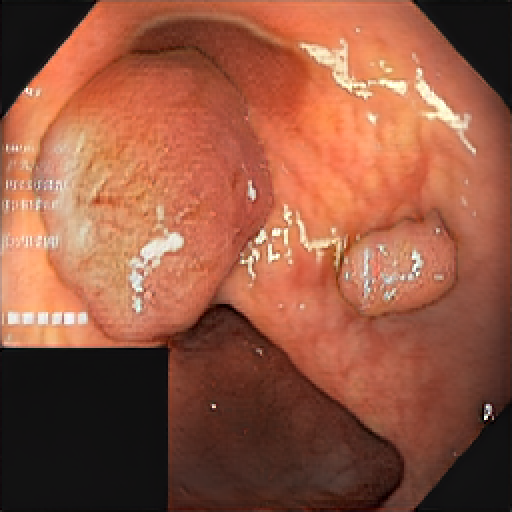

We have used a polyp dataset published with HyperKvasir dataset [51], which consists of polyp findings extracted from endoscopy examinations. HyperKvasir contains polyp images with corresponding segmentation masks annotated by medical experts. We use only this polyp dataset as a case study because of the time and resource-consuming training process of the SinGAN-Seg pipeline. However, the SinGAN-Seg model and pipeline can be used for any segmentation dataset.

A few sample images and the corresponding masks of the polyp dataset in HyperKvasir are shown in Fig 2. The polyp images are RGB images. The masks of the polyp images are single-channel images with white () for true pixels, which represent polyp regions, and black () for false pixels, which represent clean colon or background regions. In this dataset, there are different sizes of polyps. The distribution of polyp sizes as a percentage of the full image size is presented in the histogram plot in Fig 3, and we can observe that there are more relatively small polyps compared to larger polyps. Additionally, a subset of this dataset was used to prove that the performance of segmentation models trained with small datasets can be improved using our SinGAN-Seg pipeline, and the whole dataset was used to show the effect of using SinGAN-Seg generated synthetic images instead of a large dataset which has enough data to train segmentation models. In this regard, this dataset was used for two purposes: